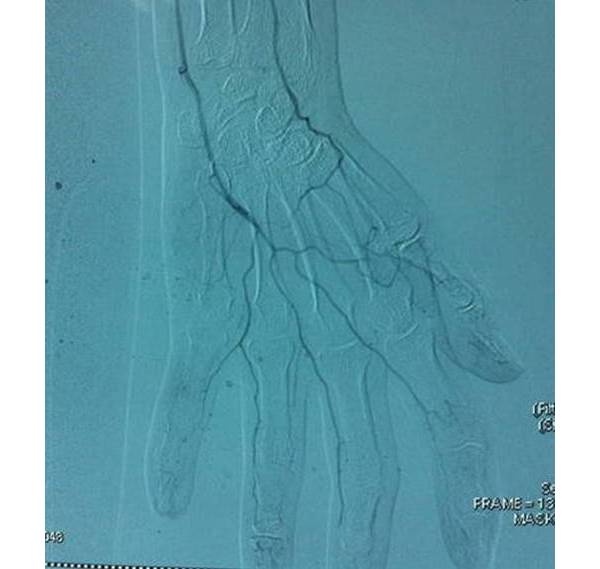

不要把掌浅弓太当成弓

其实这个弓极不规则,图谱画得太理想化了。